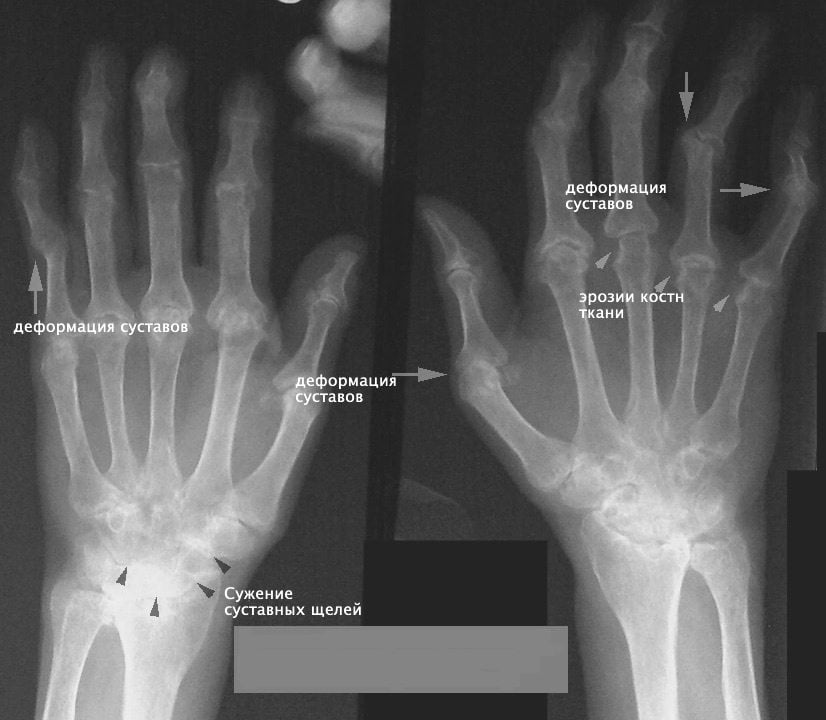

| Изменения на рентгенограммах | Для РА характерно появление околосуставного остеопороза, кистовидных просветлений костной ткани, эрозий, вывихов, деформации суставов | При остеоартрозе у больных выявляют сужение суставных щелей, характерные костные деформации. У некоторых пациентов также появляются признаки остеопороза |